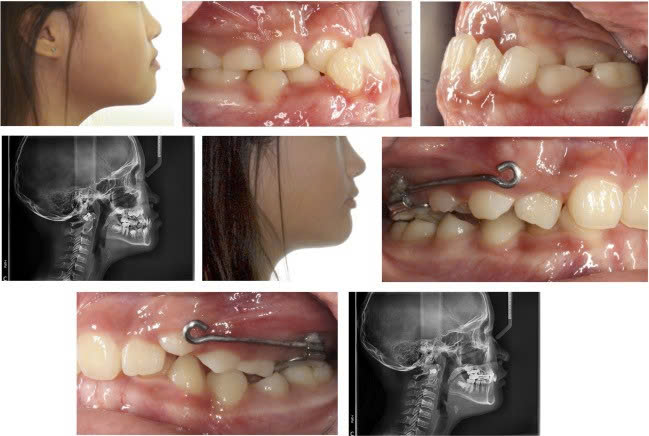

- Khí cụ cố định đơn giản (face mask, TPA, RPE, MARPE): dùng khi cần kiểm soát hoặc mở rộng xương hàm.

Nguồn: Class III treatment by combining facemask (FM) and maxillary skeletal expander (MSE), Won Moon, Seminar in Orthodontics 2018